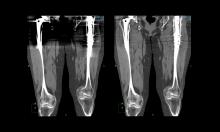

In Part 2 of this 3-part video series on recent advancements in diagnostic radiology, current editorial advisory board member Robert L. Bard, MD, PC, DABR, FASLMS, talks with ITN on the advantages of using power Doppler Sonography as a non-invasive way to screen for prostate tumors with abnormal blood vessels.

Dr. Bard is internationally known and recognized as a leader in his field. He specializes in advanced 3-D Doppler imaging to detect cancers in numerous organs, including the breast, prostate, and other areas. His images are used to accurately guide biopsies, target therapy and provide focused follow-up after treatment. He is committed to improving non-invasive cancer testing and developing minimally invasive image guided technologies to prevent cancer spread.